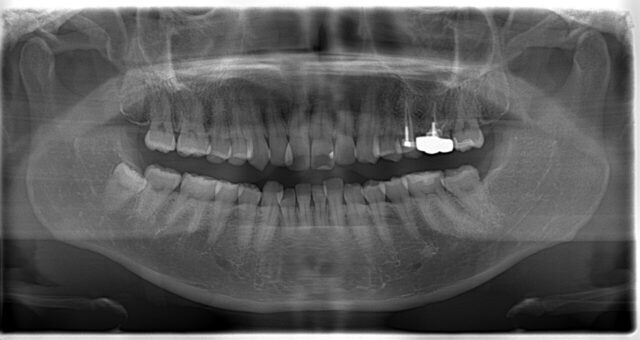

まずは初診時のパノラマと5枚法をご覧下さい!

右上の2番目だけ大きく内側に入ってしまっています。また、下の前歯も少しがたつきがあります。

この歯並びでは審美的な問題に加えてもうひとつ問題があります。